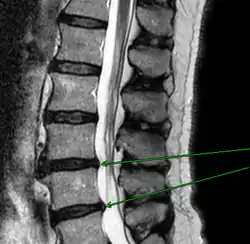

Механическое смещение одного из поясничных позвонков, переохлаждение, локальная инфекция, опухоли, деградация тканей, могут привести к воспалительному процессу в позвоночно-двигательном сегменте, последующим мучительным болям, вынужденным положениям тела. Очень распространённой причиной патологии в поясничном отделе позвоночника является неверное распределение нагрузки на поясничный отдел позвоночника, когда дополнительный вес (а иногда и собственный вес) поднимаются с единственным рычагом в поясничном отделе позвоночника. Частым заболеванием в поясничном отделе позвоночника являются грыжи межпозвоночных дисков — выпячивания пульпозного ядра диска за пределы его фиброзного кольца. В 48 % случаев межпозвоночные грыжи локализуются на уровне L5-S1 пояснично-крестцового отдела, в 46 % случаев — на уровне L4-L5, и лишь в оставшихся 6 % случаев — между другими позвонками поясничного, шейного или грудного отделов позвоночника.